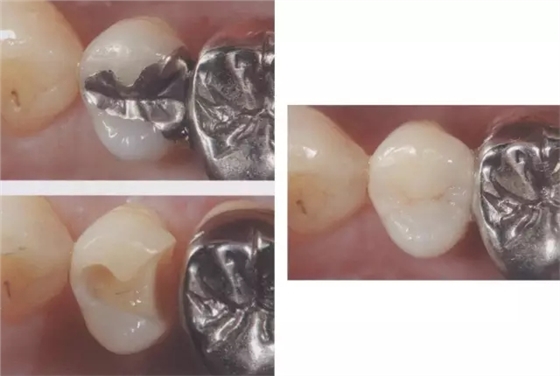

圖2右5進(jìn)行了全瓷嵌體修復(fù),為了使受力均勻,線角需要呈圓弧狀。

圖3 全瓷嵌體的修復(fù)(右56)。鄰接面產(chǎn)生齲齒的情況(上段,中段左),去除齲齒,并佩戴嵌體(下端)。